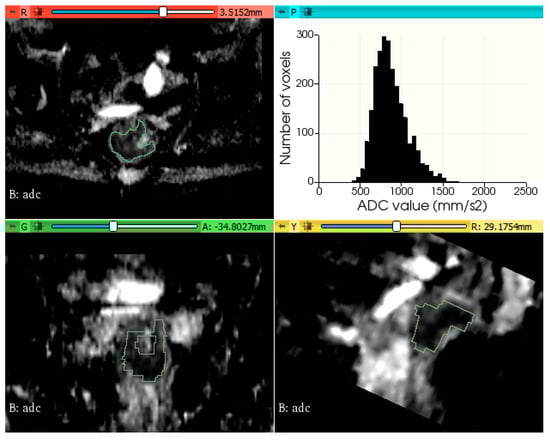

2.3. Tumor Segmentation and Feature Extraction